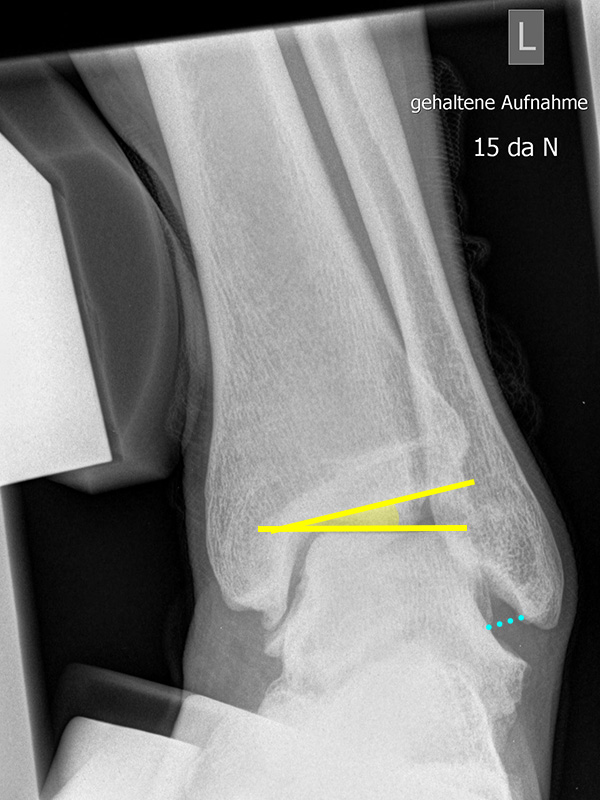

Stressaufnahme des oberen Sprunggelenks lateral

Position:

• Patient in Seitenlage auf dem Röntgentisch, zu untersuchender Fuß unten und seitlich auf der Röntgenkassette liegend (Achse des Fußes parallel zum Zentralstrahl).

• Zentralstrahl mittig auf das obere Sprunggelenk fokussiert.

• Film horizontal auf dem Röntgentisch.

• Röntgenröhre 0° vertikal.

• Der Fuß liegt in der Haltevorrichtung (z.B. Telos-Gerät, Scheuba-Apparat). Die Ferse wird von dorsal stabilisiert.

• Von ventral wird über die Tibia ein kontrollierter Druck von bis zu 15 daN (Dekanewton, entspricht ca. 15 kg) aufgebaut.

Kennzeichen des Röntgenbildes:

• Laterale Abbildung des oberen Sprunggelenks.

• Beurteilung der Translokation des Talus nach ventral (Talusvorschub).

• Gemessen wird die Verschiebung der Tibiaachse gegenüber der Talusachse.

• Als pathologisch gelten Talusvorschub > 2 mm im Seitenvergleich oder absoluter Talusvorschub > 4 mm.

Besondere Bemerkungen zum Beispielbild:

• Abbildung des oberen Sprunggelenks lateral.

• Fremdkörper in den plantaren Weichteilen in Höhe der plantaren Begrenzung des Kalkaneus.

Anmerkung:

• Belastungsaufnahmen können sowohl manuell gehalten, als auch mit verschiedenen Hilfsgeräten durchgeführt werden. Standard ist eine Druckapplikation von 15 kp. In der akuten Verletzung ist eine Stressaufnahme nur unter Analgesie (z.B. Lokalanästhesie des Kapsel-Band-Apparats) aussagekräftig. Für den Behandlungsalgorithmus nach Außenbandverletzung spielt die gehaltene Aufnahme heute nur noch eine untergeordnete Rolle. Bei unklaren Befunden ist ein Vergleich mit der Gegenseite möglich; dieses zwangsläufig mit einer höheren Strahlendosis belastete Vorgehen sollte aber nicht zur Kompensation mangelnder röntgenmorphologischer und anatomischer Kenntnisse verwendet werden.